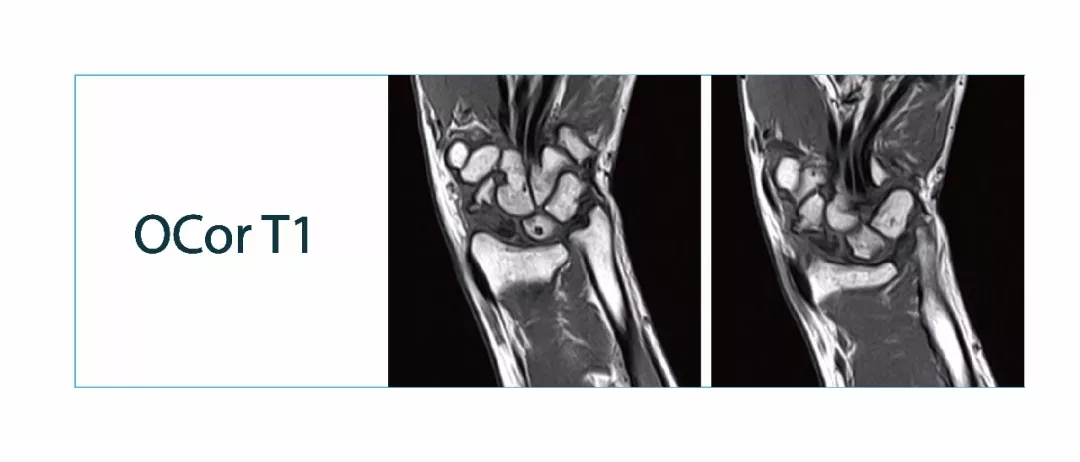

【朗润影像档案】20180126磁共振影像病例结果讨论